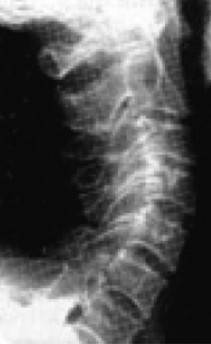

Второй вариант деформации шейного отдела – это, наоборот, спрямление физиологического изгиба шеи (рис. 13а), превращающее ее в «палку». Обычно этот процесс не связан напрямую с возрастом. Чаще всего тут виновен не возрастной синдром, а другие патологии опорно-двигательного аппарата.

Рис. 13а. Спрямление шейного отдела